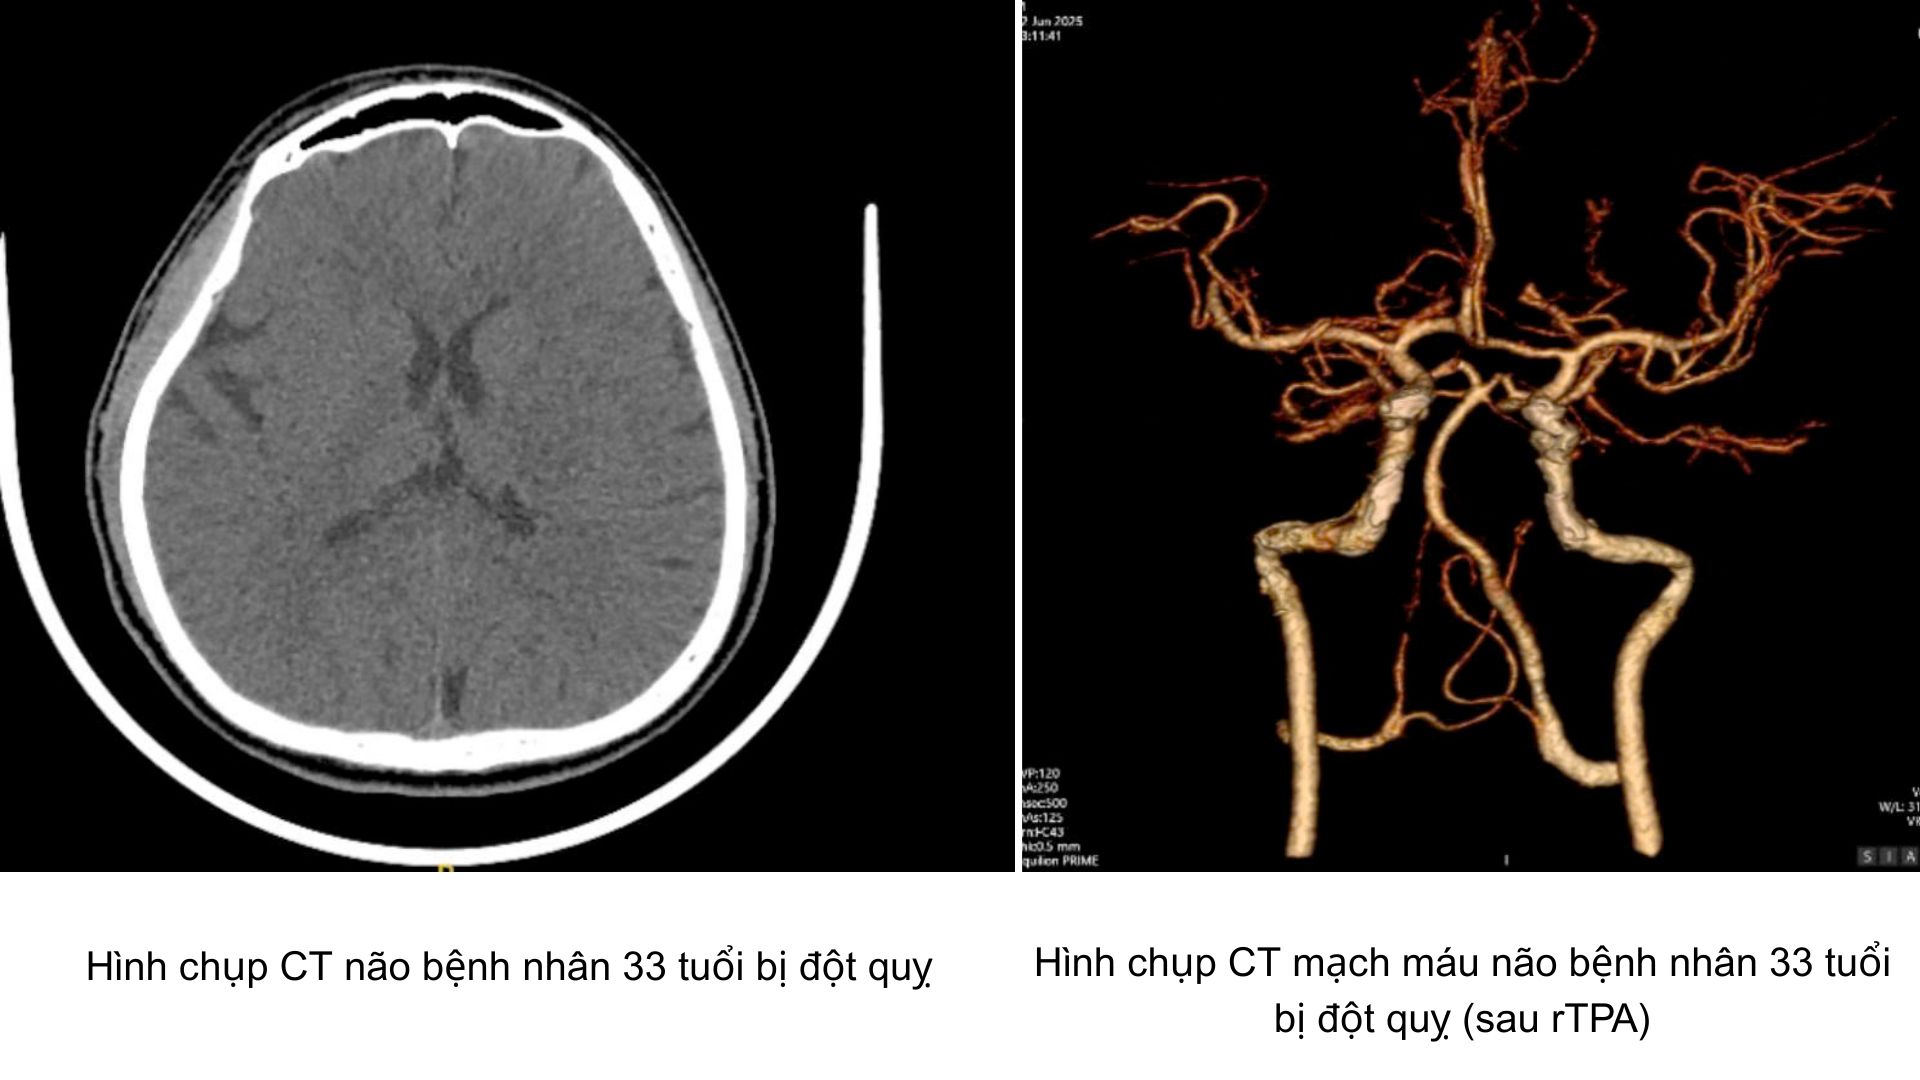

Nam thanh niên 33 tuổi khỏe mạnh đột ngột đột quỵ

Dù không có tiền sử bệnh lý, một nam thanh niên 33 tuổi ở Long An bất ngờ bị đột quỵ khi đang làm việc giữa trưa nắng tại công trình xây dựng. Nhờ được đưa đến bệnh viện kịp thời và xử trí đúng quy trình “giờ vàng”, bệnh nhân đã vượt qua cơn nguy kịch, hồi phục gần như hoàn toàn sau 1 tuần điều trị.